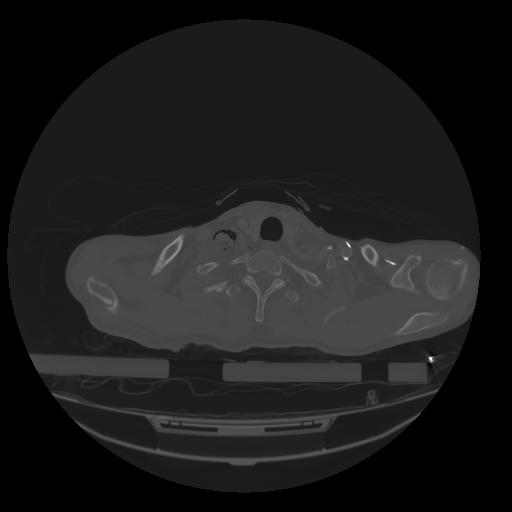

28 CUERPO,CE,Vol,2.0,CUERPO,,